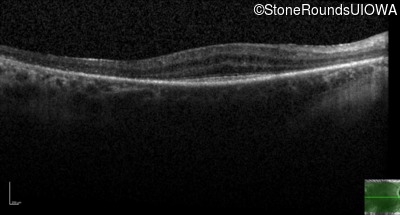

Age at visit: 49 years (Visit 2)